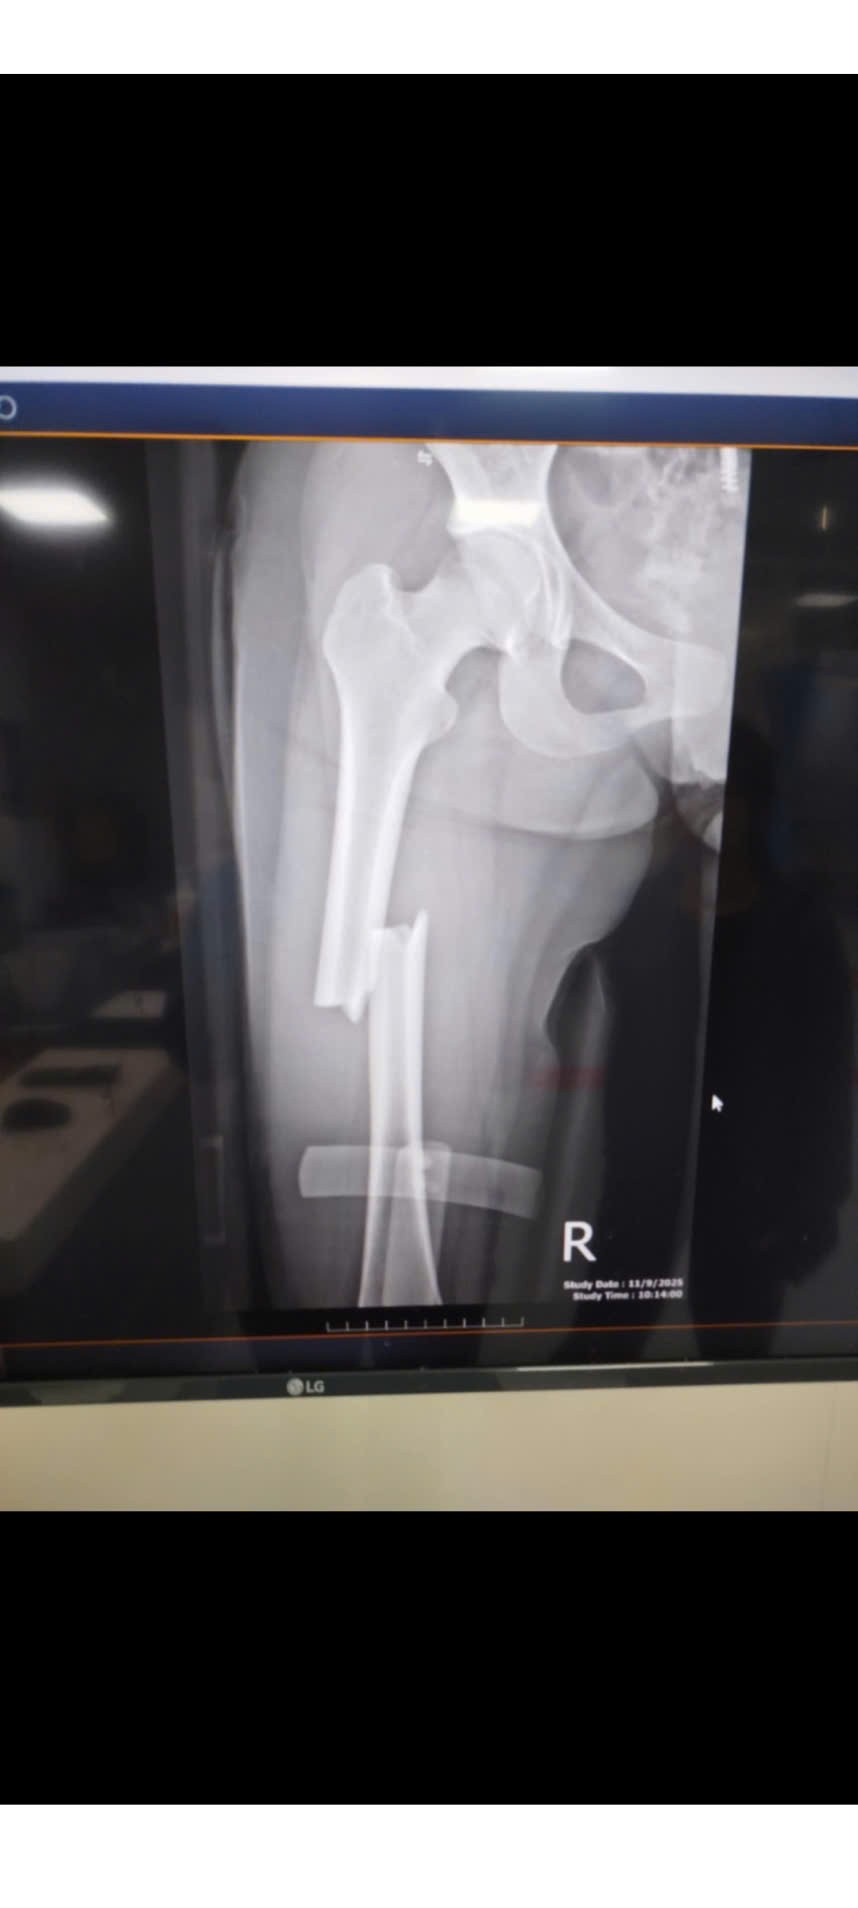

Chiều ngày 9/11/2025, trên đường từ Nam Đàn trở về nhà tại Thanh Chương, em Hoài không may gặp tai nạn giao thông nghiêm trọng, khiến em bị gãy xương đùi 3 đoạn, gãy 1 răng cửa, nhiều răng khác bị tổn thương.

Ngay sau đó, Hoài được đưa đến Bệnh viện 115 Nghệ An và tiến hành phẫu thuật khẩn cấp trong cùng ngày. Chi phí điều trị và phục hồi dự kiến còn rất lớn, vượt xa khả năng của gia đình.